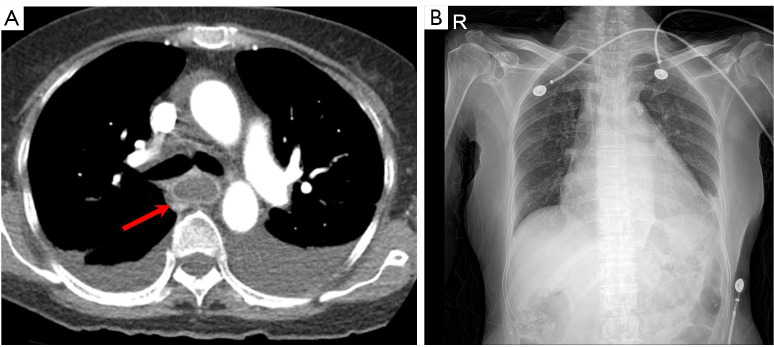

Case description: A 65-year-old woman was admitted to Inje University Sanggye Paik Hospital with general weakness, abdominal discomfort, nausea and chest discomfort. On chest and abdominal radiographs, there were abnormal air density in upper mediastinum and abdomen. Chest and abdomen computed tomography (CT) revealed mural air at entire esophagus and stomach. The patient managed with proton pump inhibitor (PPI), broad spectrum antibiotic therapy, and total parenteral nutrition (TPN).